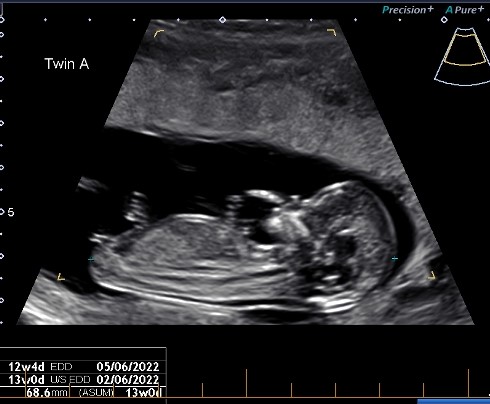

Hello, would anyone be keen to guess the genders of these 2? No good pics of baby B but baby A seems to have a clear nub. Thanks so much!